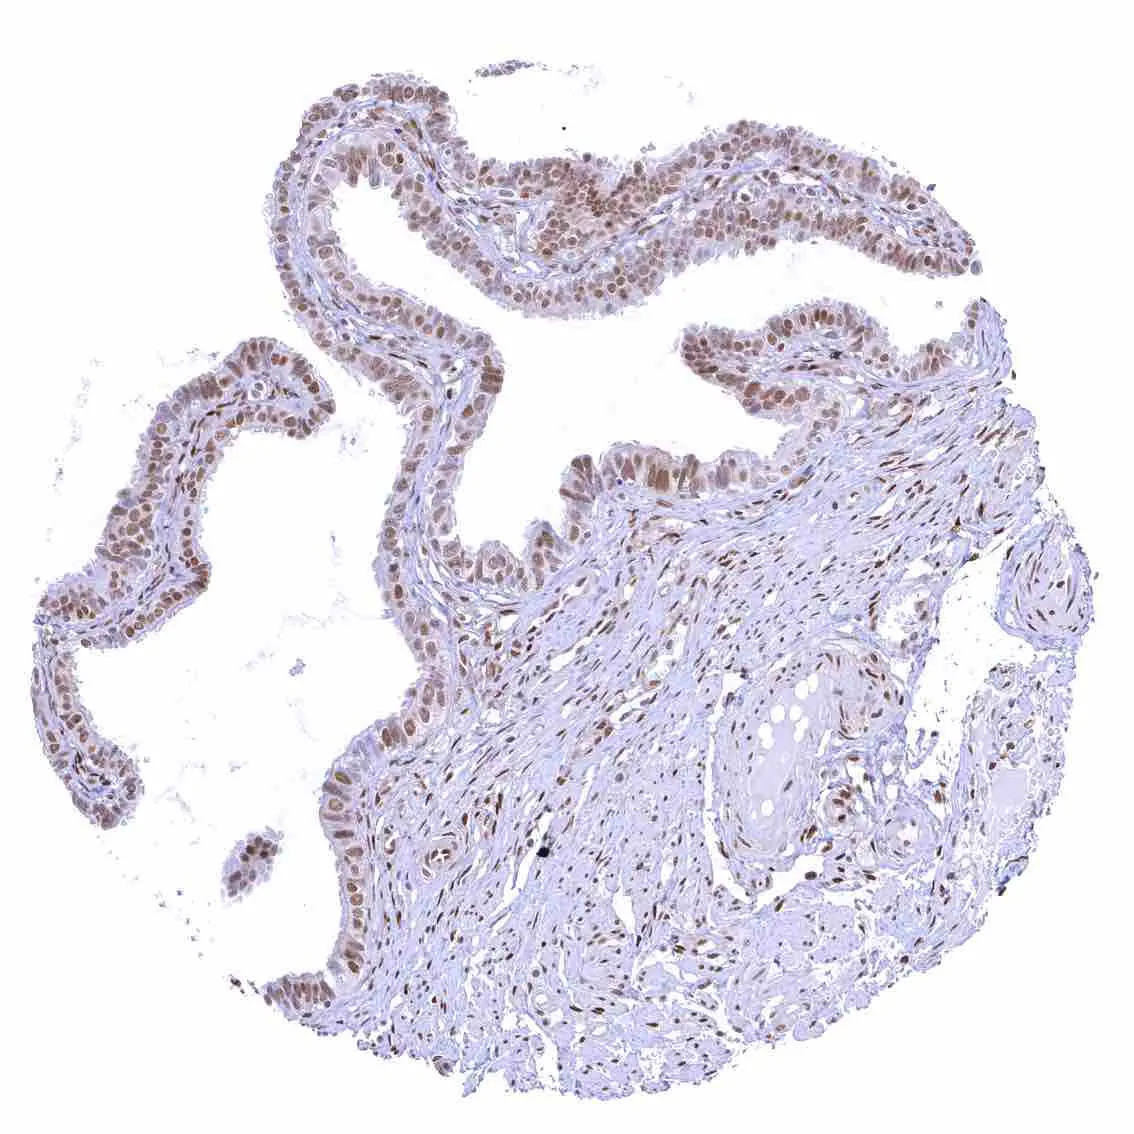

Uterus, endocervix – Nuclear p27 staining is variable in the endocervix. It is positive in all epithelial cells in this sample.